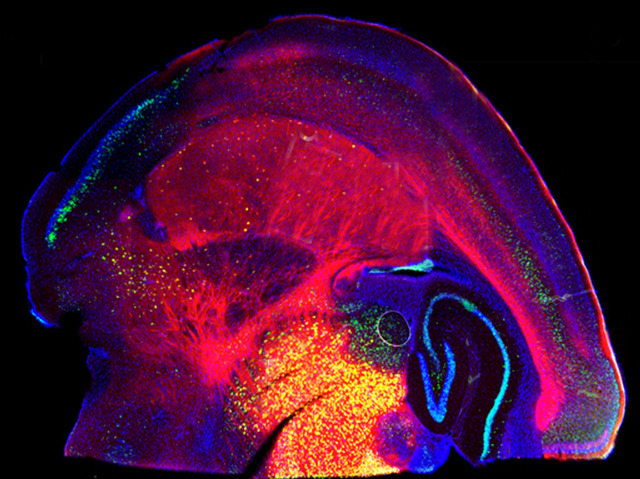

On a long journey, one wrong turn early on can send you off in completely the wrong direction, whereas a misstep near the destination might be easily rectified. Similarly, when things go awry in early development, while the body is still putting itself together, the repercussions can be severe. Tuberous sclerosis complex is a disease that causes abnormal growths around the body, and can also cause mental disabilities and seizures. It is caused by a genetic mutation in the brain that occurs early in embryonic development. Now researchers have found that the timing of this mutation dictates the intensity of the symptoms. When the mutation occurred in the brain of an 18-day-old mouse embryo (pictured), the symptoms were much less severe than for those who experienced the mutation after 12 days. This discovery might lead the way to new treatments, and shows that timing really is everything.